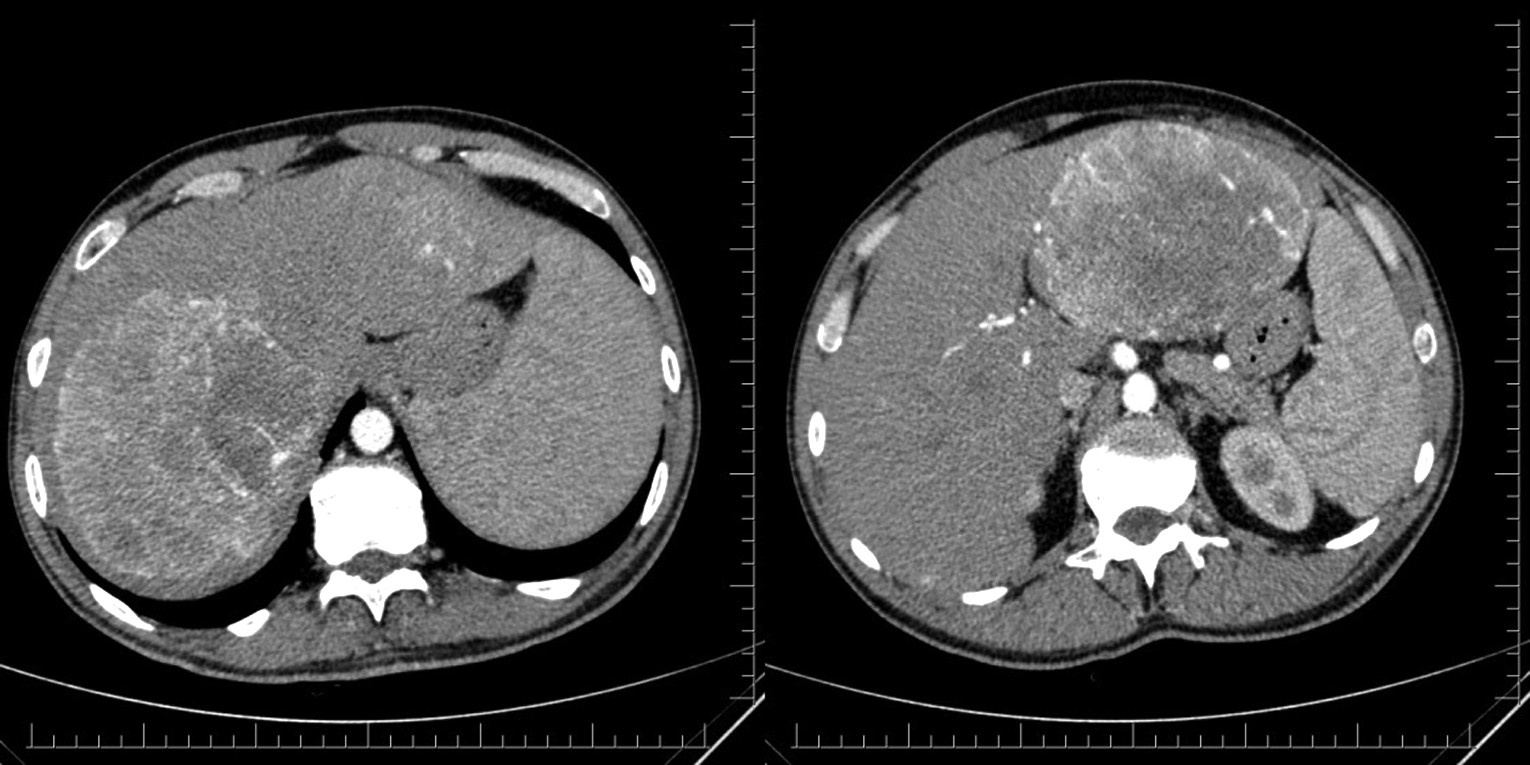

При динамической МРТ с контрастным усилением гадоксетовой кислотой (рис. 2) выявлены увеличенные размеры печени (вертикальный размер правой доли 24 см, левой доли 18 см, горизонтальный 21 см), контуры четкие, ровные, при контрастном усилении интактная паренхима повышает плотность максимально в портальную и гепатоспецифическую фазы, в Sg7–8 печени визуализировано патологическое тканевое образование шаровидной формы, с максимальным размером 12×13 см, с неровными крупнобугристыми контурами, неоднородное по структуре, в Sg2–3 визуализировано аналогичное патологическое тканевое образование шаровидной формы 9×13 см; оба образования максимально интенсивно аккумулируют контрастный препарат в артериальную фазу, в паренхиме печени визуализированы многочисленные шаровидной формы разнокалиберные очаги (от 5 до 20 мм в диаметре) с четкими и ровными контурами, однородные по структуре, других изменений органов брюшной полости и забрюшинного пространства не выявлено. Заключение: томографические признаки соответствуют гепатоцеллюлярной карциноме с множественным билобарным поражением.

Рис. 2. МРТ: динамическое сканирование печени в аксиальной проекции на импульсной последовательности LAVABHAsset с использованием гадоксетовой кислоты (описание в тексте).